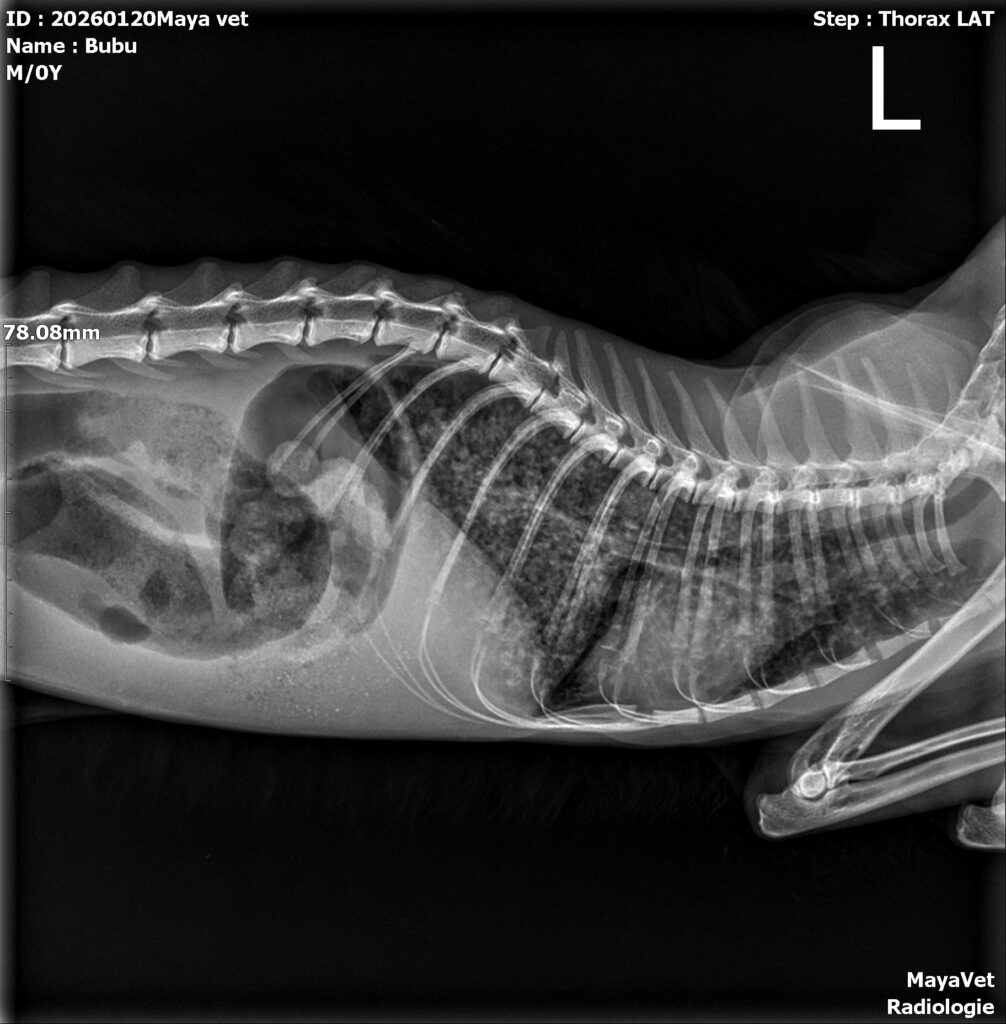

Ce ne îngrijorează: Respirația este încă îngreunată. Radiografia toracică ne-a confirmat ceea ce ne temeam: Bubu se luptă cu probleme pulmonare severe. Va avea nevoie de tratament prelungit și de urmărire atentă din partea medicilor.

Radiografia toracică a fost oferita gratuit. La tot ce a fost posibil s-a aplicat o reducere de 50%.